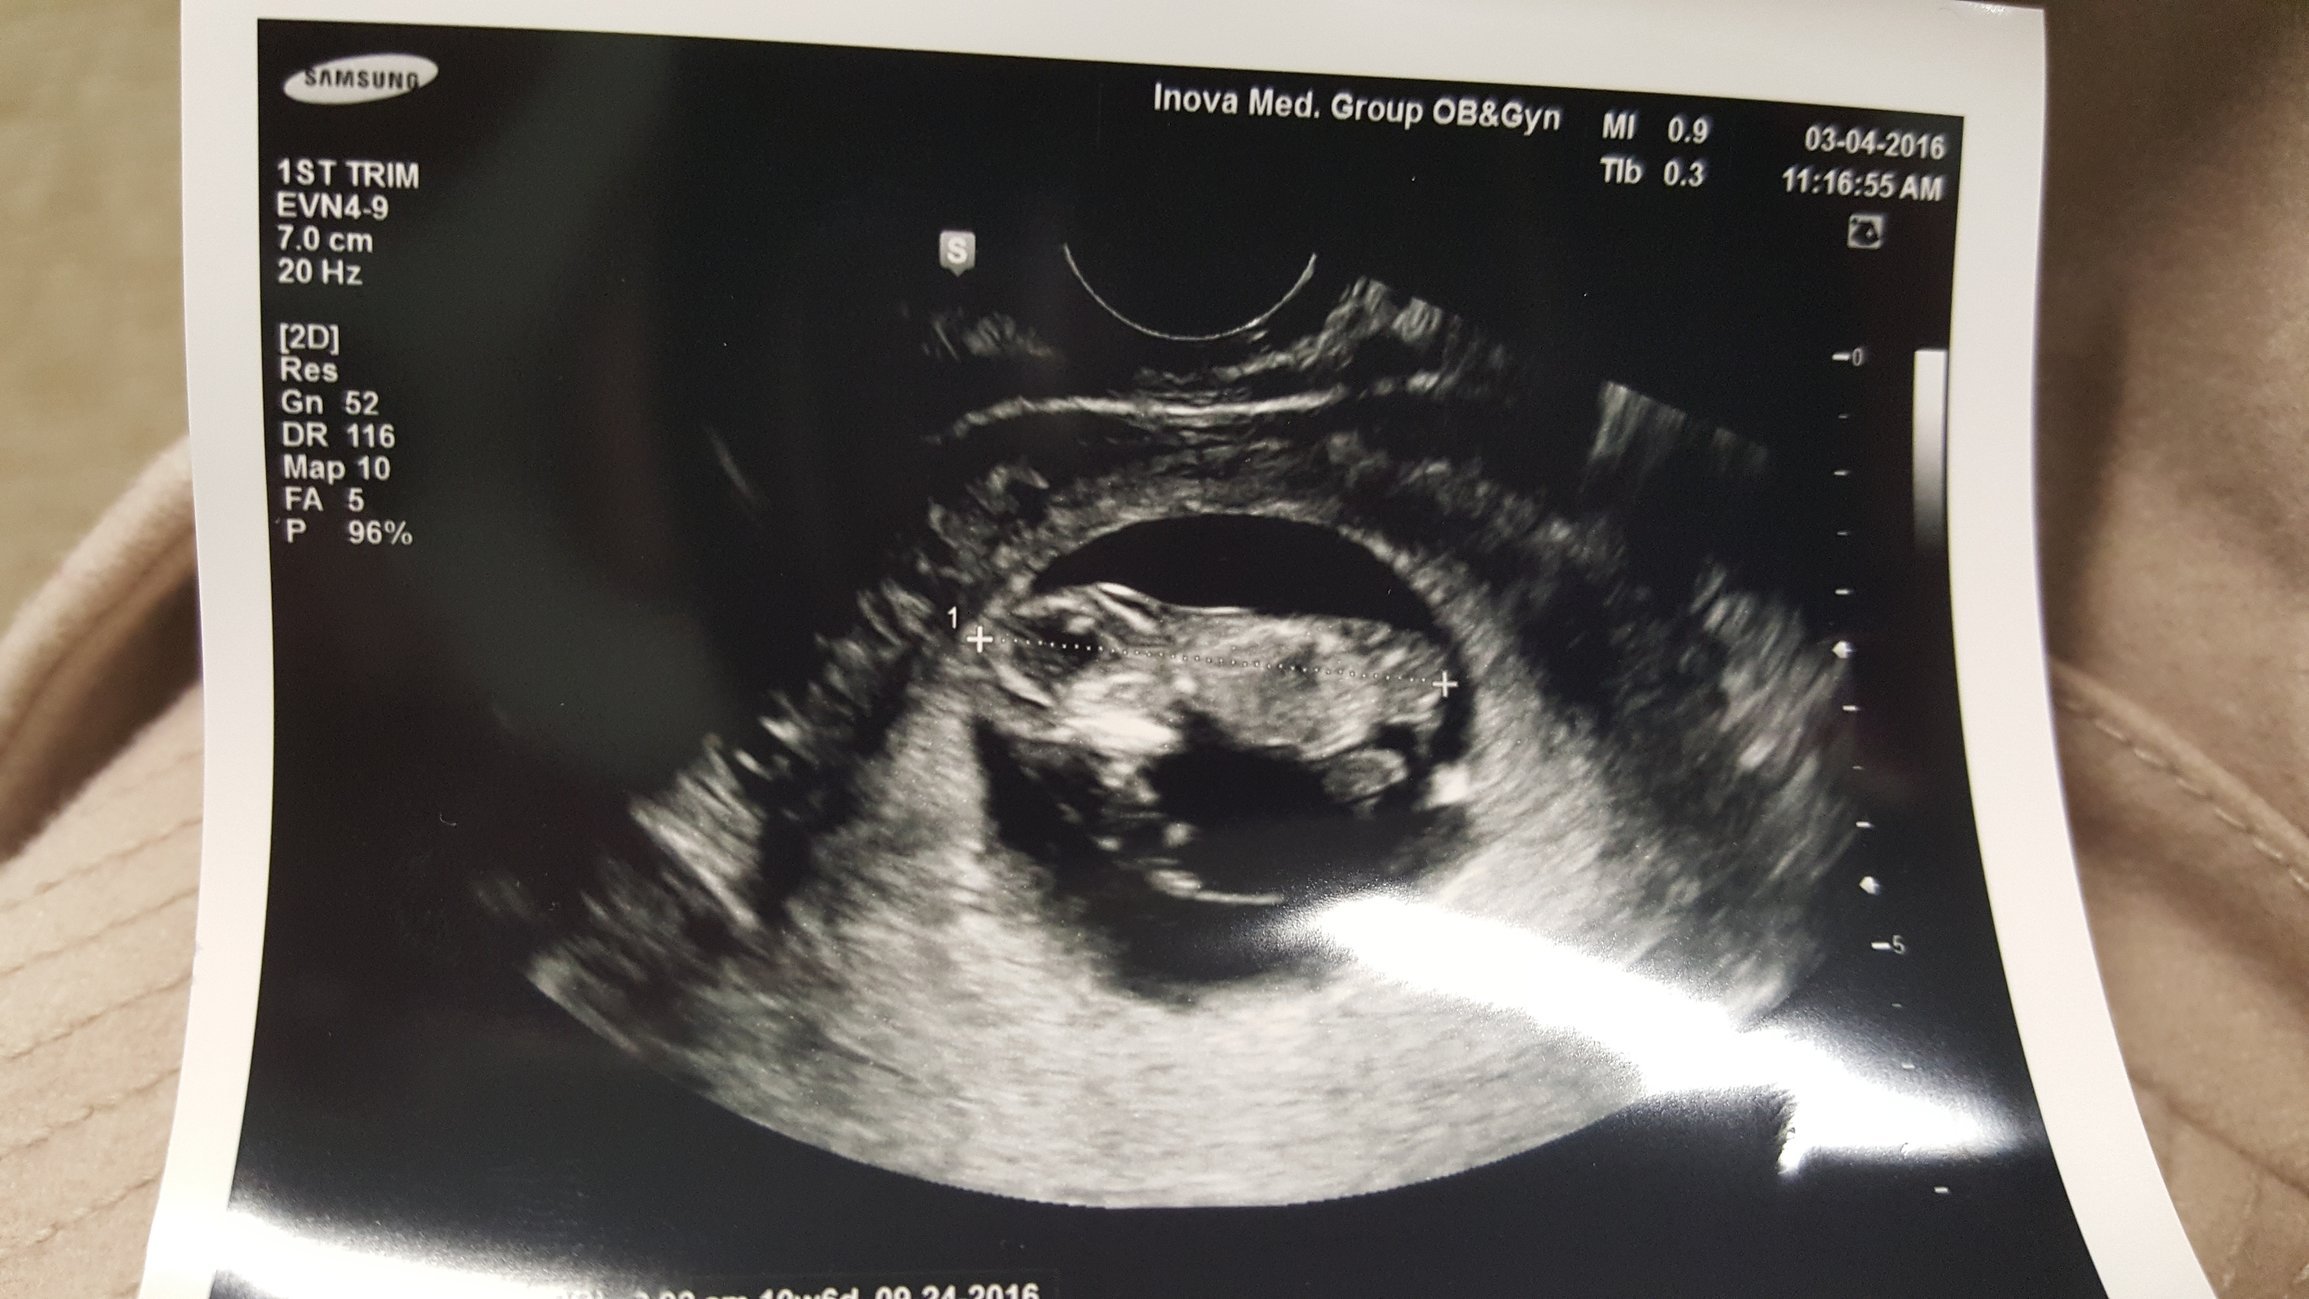

Finally! Met our rainbow baby yesterday, measuring spot on at 10w+1 and heartbeat at about 150/min. LO had the sweetest hiccups that we could see on the u/s, I'm in love!